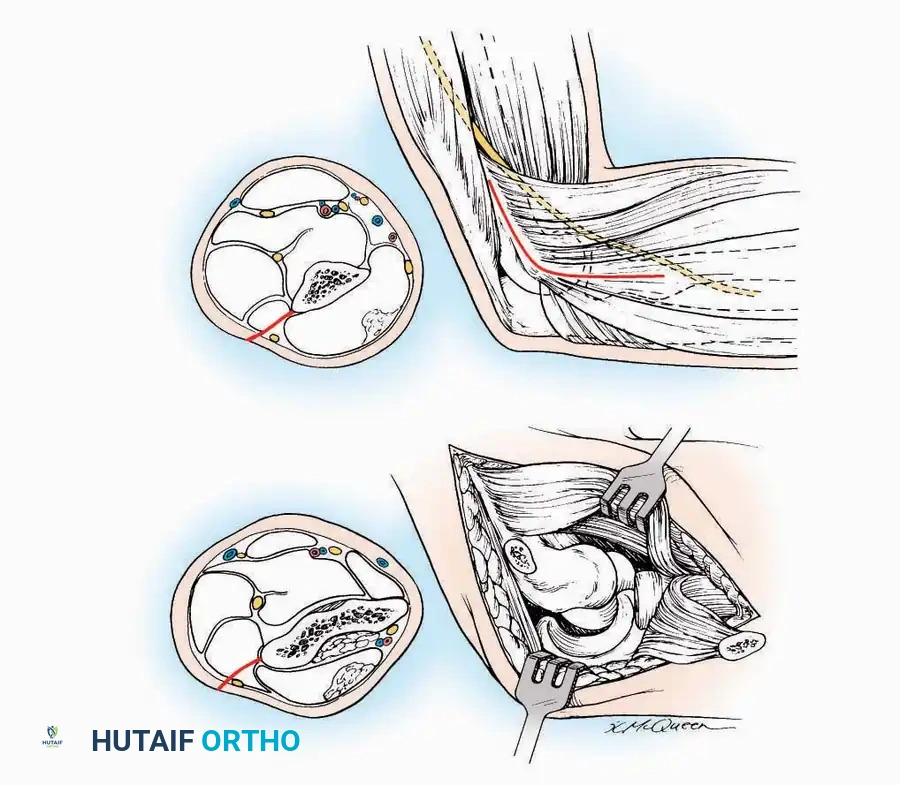

Lateral Approach (Extensile Lateral)

This is the workhorse approach for open reduction and internal fixation (ORIF) of displaced intra-articular calcaneal fractures.

Indications: ORIF of calcaneus fractures, lateral wall exostectomy, subtalar arthrodesis.

Positioning: Lateral decubitus with the operative leg up, or supine with a large bump under the ipsilateral hip to internally rotate the leg.

Surgical Technique:

* Incision: Begin the incision on the lateral margin of the Achilles tendon near its insertion. Extend it distally to a point 4 cm inferior and 2.5 cm anterior to the lateral malleolus. (For trauma, a classic L-shaped extensile incision is often used, dropping straight down anterior to the Achilles, then curving gently toward the base of the 5th metatarsal).

* Superficial Dissection: Divide the superficial and deep fasciae. It is imperative to create a "full-thickness" flap containing skin, subcutaneous fat, and periosteum to prevent flap necrosis.

* Nerve Protection: The sural nerve crosses the proximal and distal limbs of this approach. It must be identified and protected within the anterior flap.

* Deep Dissection: Isolate the peroneal tendons (longus and brevis). Incise and elevate the periosteum below the tendons to expose the lateral wall of the calcaneus.

* Tendon Management: If severe deformity or infection is present, the peroneal tendons may be divided via Z-plasty and repaired at the conclusion of the case, though this is rarely necessary in modern fracture care.

Medial Approach

Indications: Fixation of sustentaculum tali fractures, medial process fractures, or excision of medial tarsal coalitions.

Positioning: Supine with the hip externally rotated and knee flexed (figure-of-four position).

Surgical Technique:

* Incision: Begin 2.5 cm anterior and 4 cm inferior to the medial malleolus. Carry it posteriorly along the medial surface of the foot toward the Achilles tendon.

* Superficial Dissection: Divide the fat and fascia to define the inferior margin of the abductor hallucis muscle.

* Deep Dissection: Mobilize the abductor hallucis muscle belly and retract it dorsally to expose the medial and inferomedial aspects of the calcaneal body.

* Plantar Exposure: Continue distally by dividing the plantar aponeurosis and the muscular attachments to the calcaneus, or strip them subperiosteally with an osteotome.

* Neurovascular Warning: Meticulously identify and protect the medial calcaneal nerve and the nerve to the abductor digiti minimi (first branch of the lateral plantar nerve), which are highly vulnerable during inferior retraction.